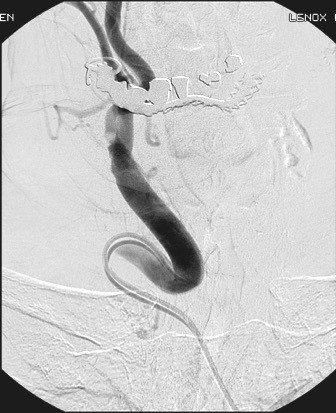

Karotis arter hastalığının tanısında en sık kullanılan testlerin başında karotis ultrason gelmektedir. Karotis ultrason ile darlığın yapısı ve ciddiyeti hakkında bilgi edinilir. Eğer karotis ultrason yetersiz kalır veya ciddi darlık saptanırsa müdehale öncesinde karotis anjiografisi yapılır.

Resim. Karotis anjioda darlık